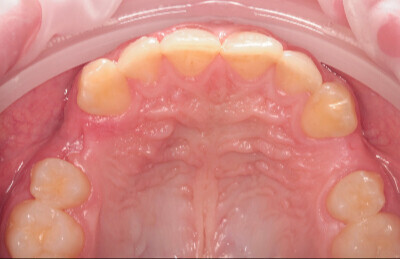

Navigovaná chirurgia, 3 implantátov

Autor práce Dr. Michal Repaši

Zubný technik Vasil Csopej